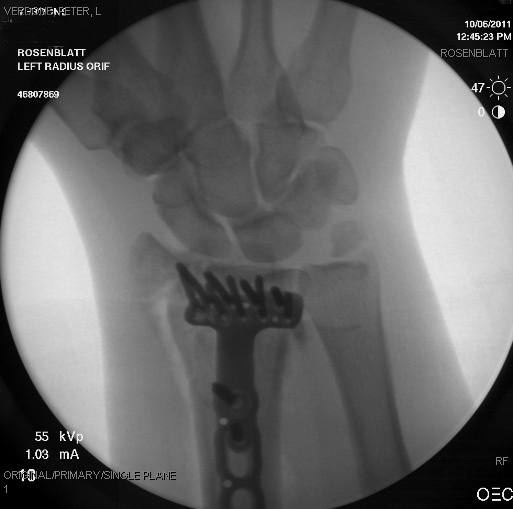

I got kicked off a big jump really bad on my warm up run. I flipped forward and landed head frist. Luckily, I didn’t break my neck. A concussion and a little swelling in my skull. I did, however, shatter my wrist. 6 peices of the radius. Sergery and 9 weeks in a cast for sure. Lot’s of new titanium bling.